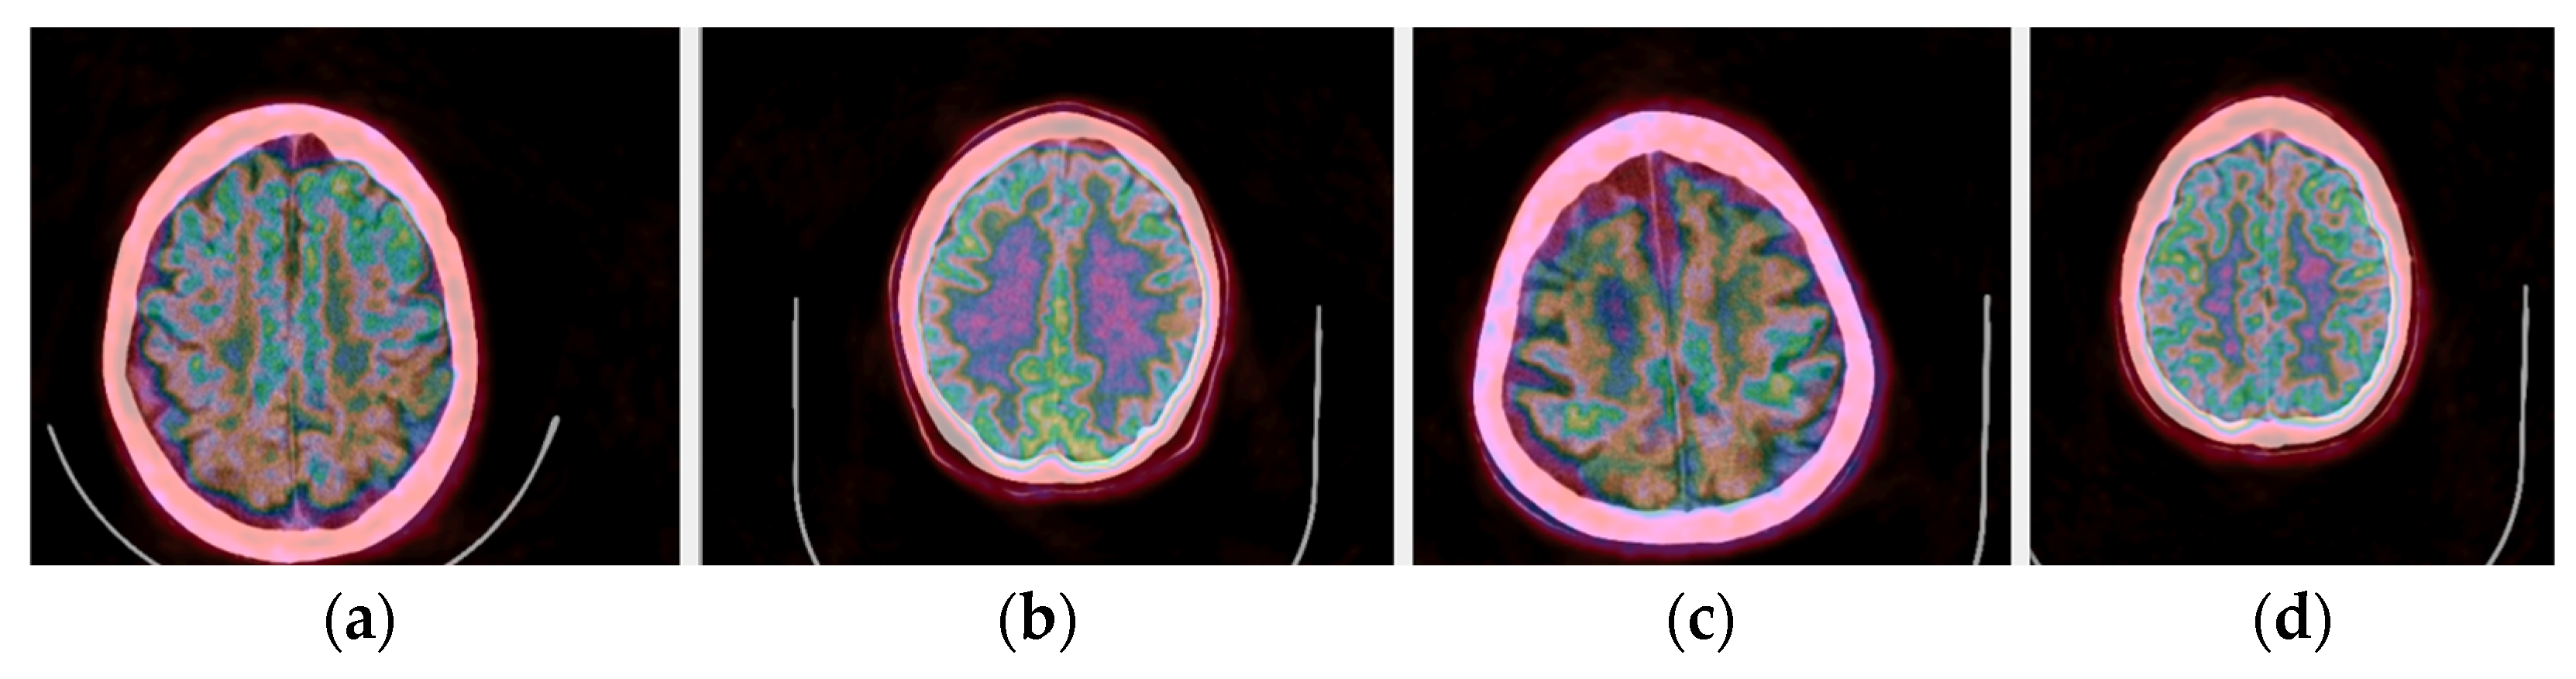

The selection of the most significant byte on the RGB tuples affects the observable noise of the transformed image. At high frequencies, the least significant byte from the Green channel in the transformation is not “friendly” to the human eye as observed in Figure 7. The “friendliest” images are obtained by a CIT where the Blue channel represents the least significant byte.

Figure 7.

(Top images series): Six CITs of a brain CT slice (left two columns) and corresponding PET slices (right two columns). 1. CIT on RGB channels giving responsibility for the most significant byte to the Red Channel, then Blue, and then Green using an equal distribution of R,G,B levels. 2. CIT on RGB channels giving responsibility for the most significant byte to Green Channel, then Blue, then Red using an equal distribution of R,G,B levels. 3. CIT on RGB channels giving responsibility for the most significant byte to Blue Channel, then Red, then Green using equal distribution of R,G,B levels. 4. CIT on RGB channels giving responsibility for the most significant byte to Blue Channel, then Green, then Red using equal distribution of R,G,B levels. 5. CIT on RGB channels giving priority for the most significant byte to Green Channel, then Red, then Blue using equal distribution of R,G,B levels. 6. CIT on RGB channels giving responsibility for the most significant byte to the Red Channel, then Green, and then Blue using an equal distribution of R,G,B levels. (Bottom image series): In this series of 18 CT images, we observe the noise that byte significance introduces into the distinct color channels. Every group of color represents the corresponding channel of the CT CIT images in the top image series.